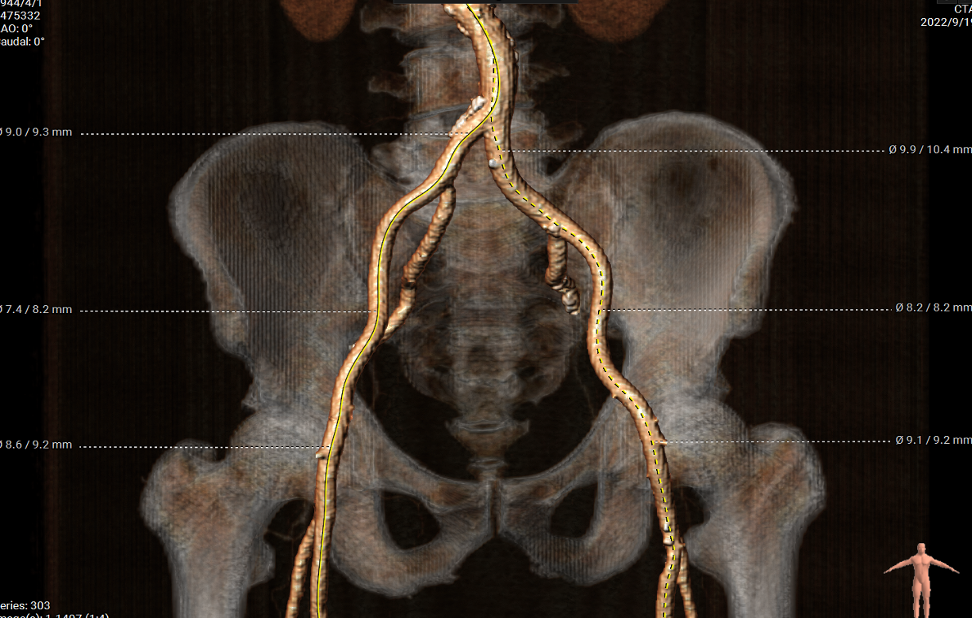

外周血管及主动脉弓解剖

双侧血管内径良好,所见腹主动脉血管壁钙化形成

手术过程概览